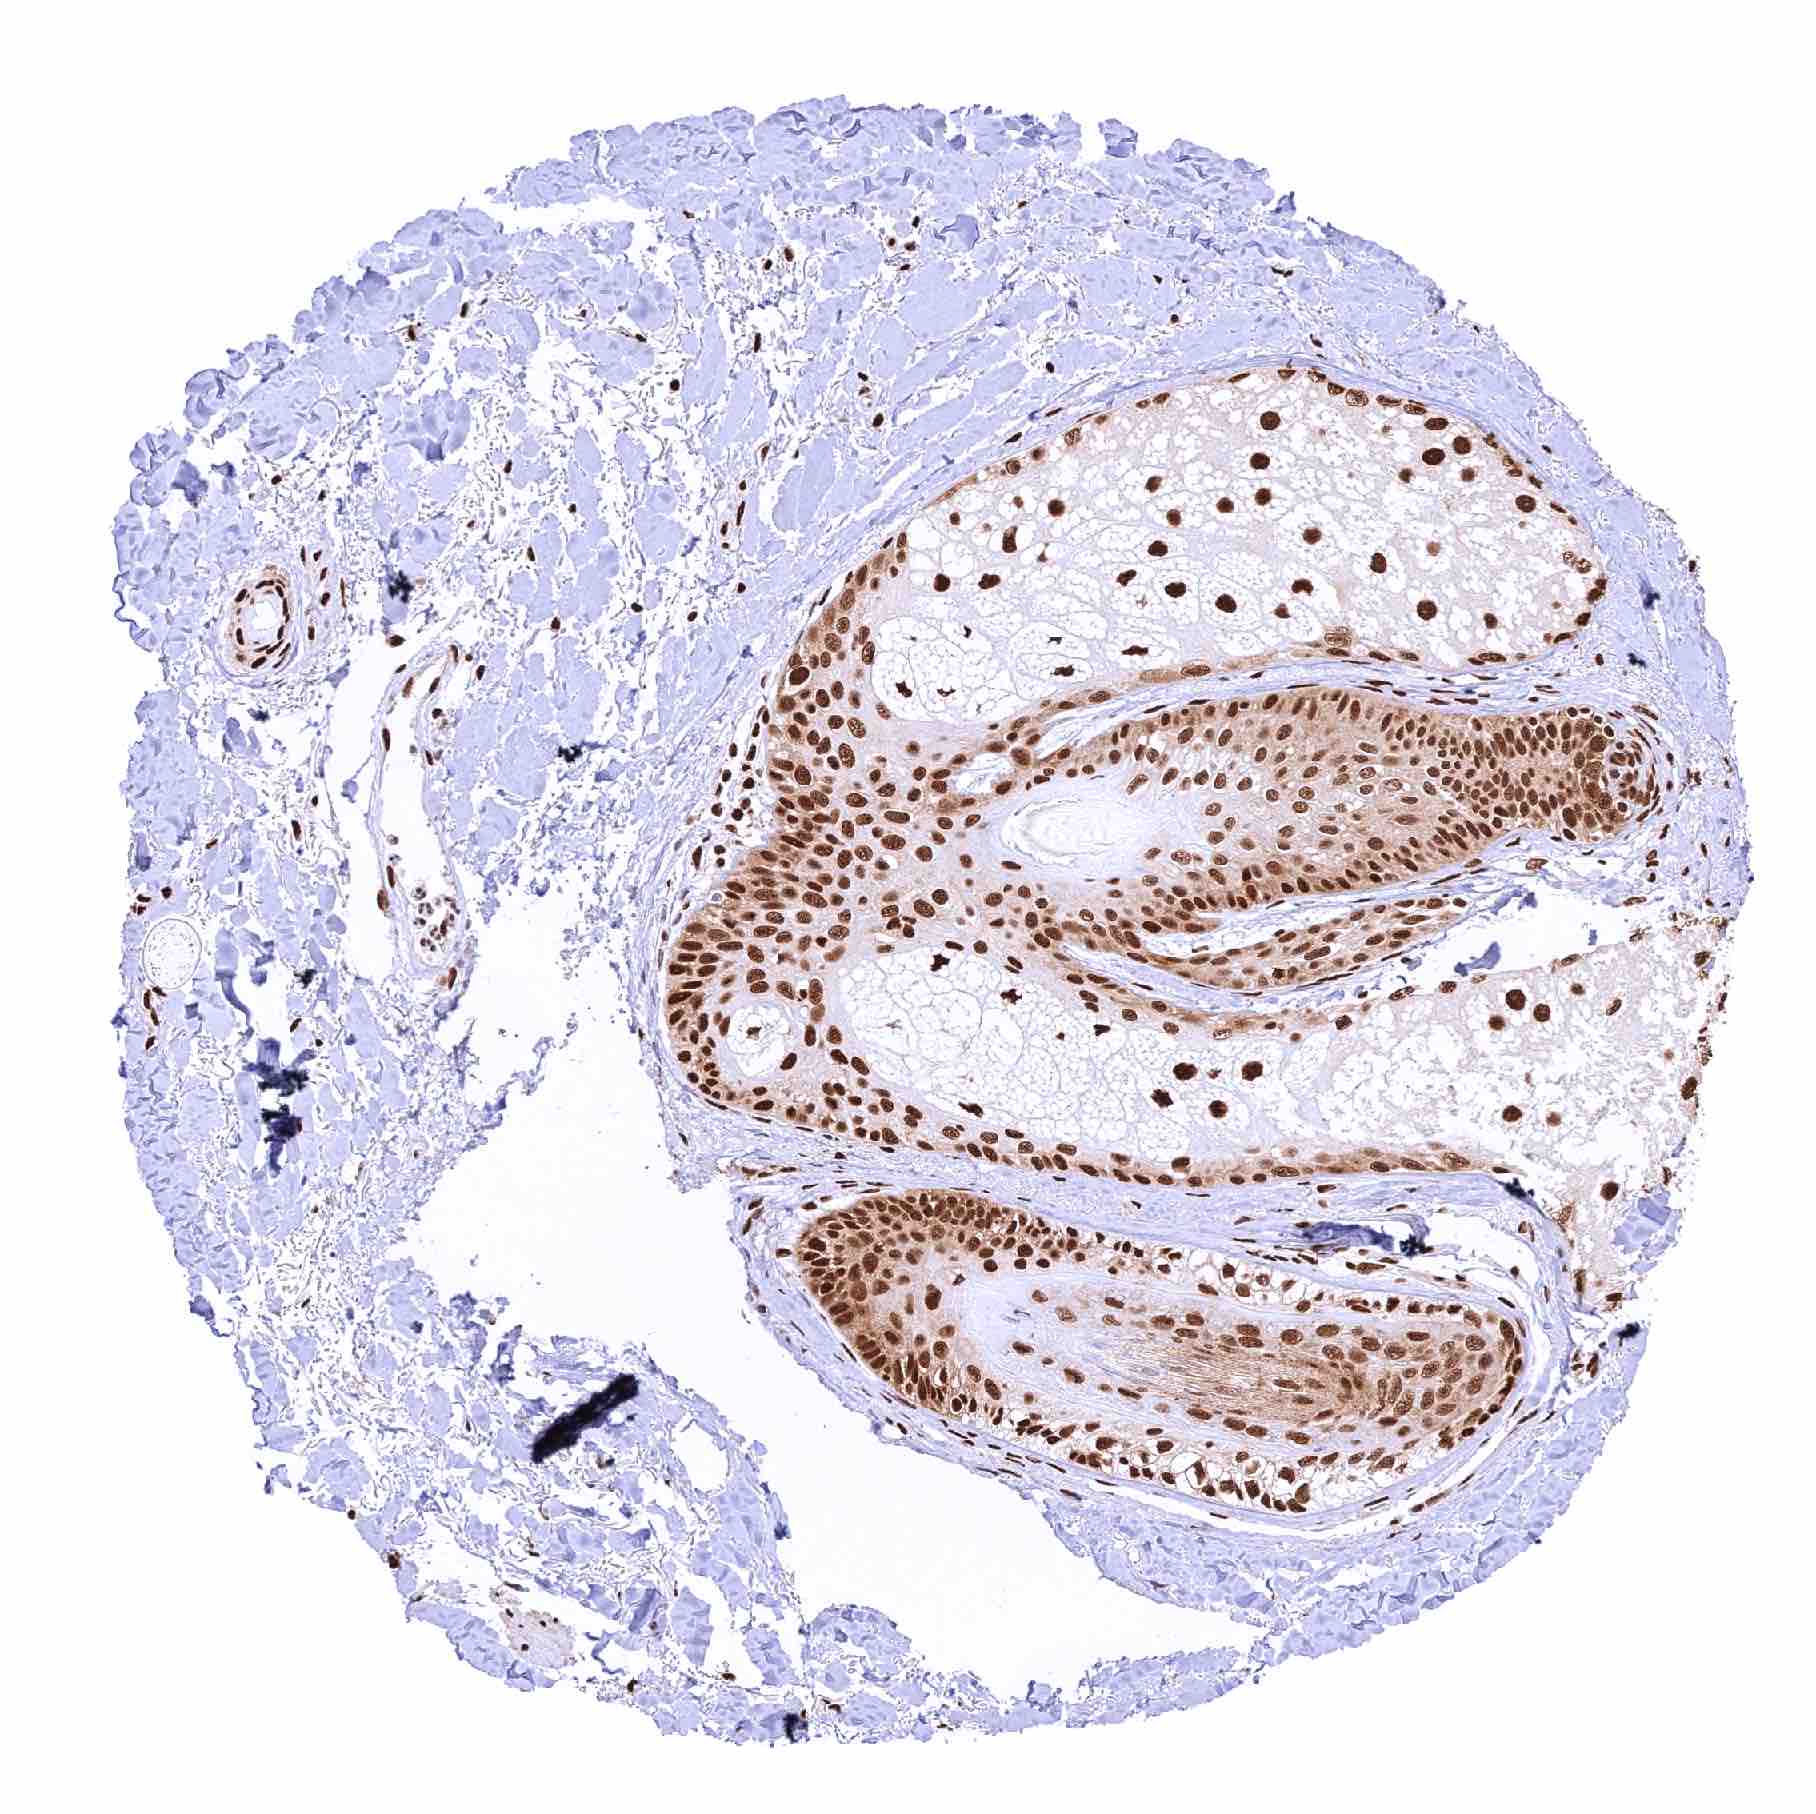

Testis – Distinct nuclear MRE11 staining of all cells although the staining intensity of germ cells decreases from spermatogonia to spermatids